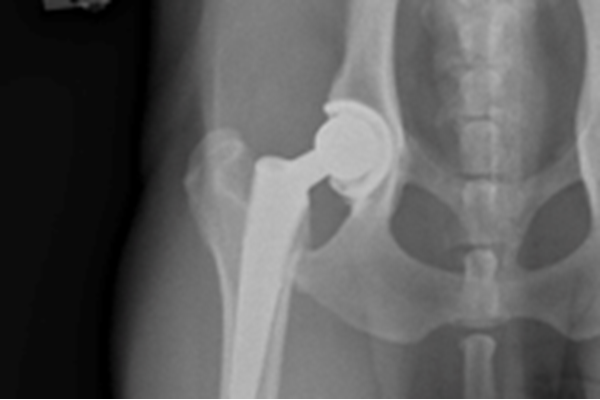

In August 2019, Bruce had a hip replacement surgery on his right hip at West Yorkshire Veterinary Referrals. The surgery was performed by Dr. Currivan, with assistance from Dr. Higson. The surgery went very well and Bruce's discomfort was so well managed that he walked on his new hip immediately after surgery!

Bruce had further x-rays taken under anaesthetic so that his pelvis and femur could be very accurately measured for the implants that would be needed.